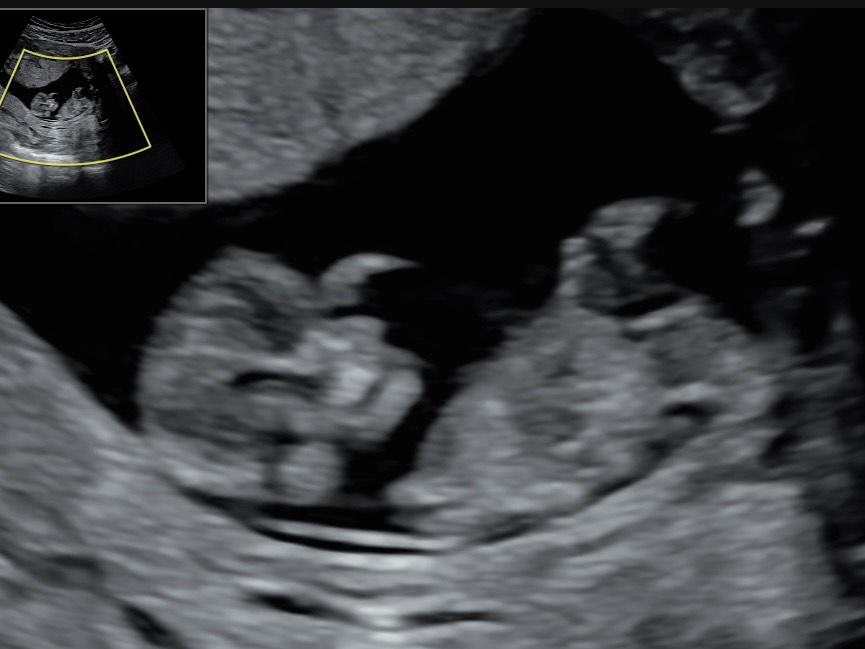

Keskiraskauden ultraääni on ajateltu erityisesti 3D-kuvia ja 4D-videoita kaipaavalle. Kuvien lisäksi tutkimuksen aikana mittaamme vauvan strategiset mitat kasvun arvioimiseksi, kuulemme sikiön sydänäänet ja voimme vielä arvailla sukupuoltakin. Käymme myös läpi vauvan rakenteita, mutta rakenneseulaa tämä ultraääni ei siitä huolimatta korvaa.

Yleensä kuvaus onnistuu parhaiten raskausviikolla 28+0 paikkeilla, mutta ei ole ollenkaan ehdoton. Kuvan laatu ja onnistumisprosentti tosin heikkenevät merkittävästi raskausviikon 32+0 myötä, mutta myös liian aikaisin, ennen 25 raskausviikkoa otetut kuvat jäävät mielestämme vauvan pienen koon vuoksi heikkolaatuisemmiksi.

Mukaan saa kuvia tulostettuna sekä sähköisessä muodossa.